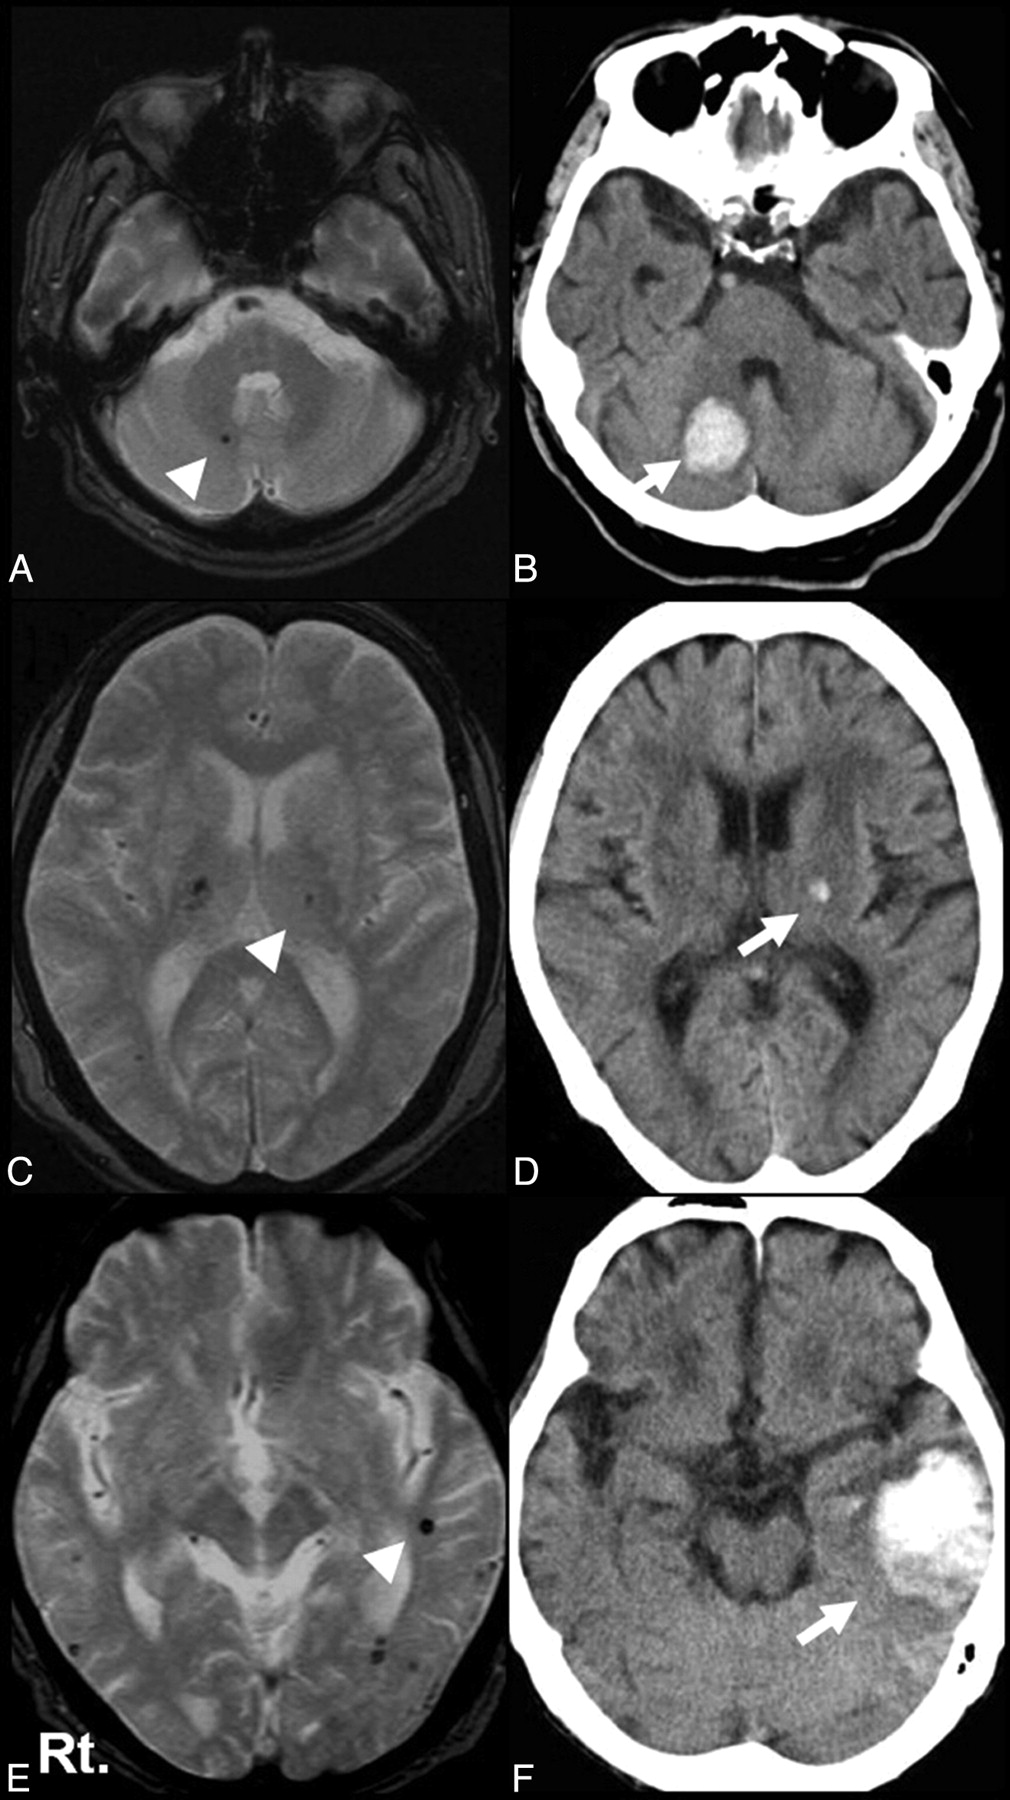

We evaluated the positional relationship between recurrent ICH/LI and previously detected MBs. In the recurrent ICH group, hematoma corresponded to the prior MBs in 21 of 34 patients (61.8%). Representative cases are shown in Fig 1. In contrast, LI corresponded to the prior MBs in only 1 of 21 patients (4.8%) in the recurrent LI group. The correspondence ratio was, therefore, higher in the recurrent ICH group than in the recurrent LI group (OR, 32.3; 95% CI, 3.86–270.3; P < .001). The number of MBs and the time from prior stroke to the recurrent stroke were equivalent between the recurrent ICH group and the recurrent LI group (Table 1).

Representative cases. T2*-weighted MR image (A) and CT scan (B) in an 84-year-old patient. Recurrent right cerebellar hemorrhage (arrow) corresponds to the location of MBs detected 9 months before (arrowhead). T2*-weighted MR image (C) and CT scan (D) in an 80-year-old patient. Recurrent left thalamic hemorrhage (arrow) corresponds to the location of MBs detected 35 months before (arrowhead). T2*-weighted MR image (E) and CT scan (F) in an 85-year-old patient. Recurrent left lobar hemorrhage (arrow) corresponds to the location of MBs detected 3 months before (arrowhead).